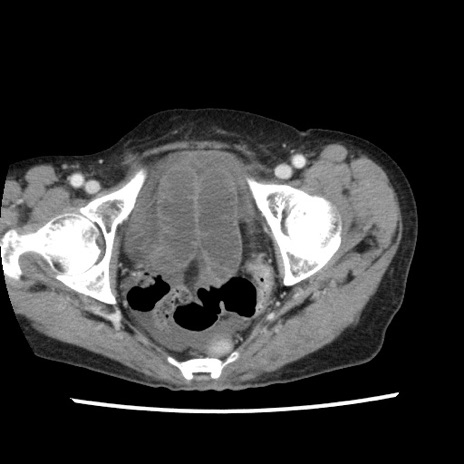

矢状断像

【症例】80歳代女性

【主訴】腹痛

【現病歴】8時間前から腹痛あり来院。

【既往歴】糖尿病、脂質異常症、子宮体癌にて子宮全摘術

【身体所見】意識清明・会話良好だが腹痛で苦悶様、全腹部にわたって反跳痛と圧痛あり

【データ】WBC 13600、CRP 0.14、LDH 224、CK 90